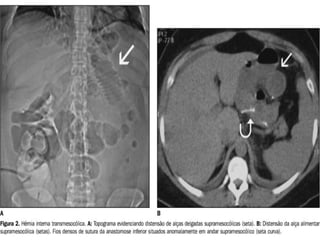

ENTERO-TC X TC ABDOME